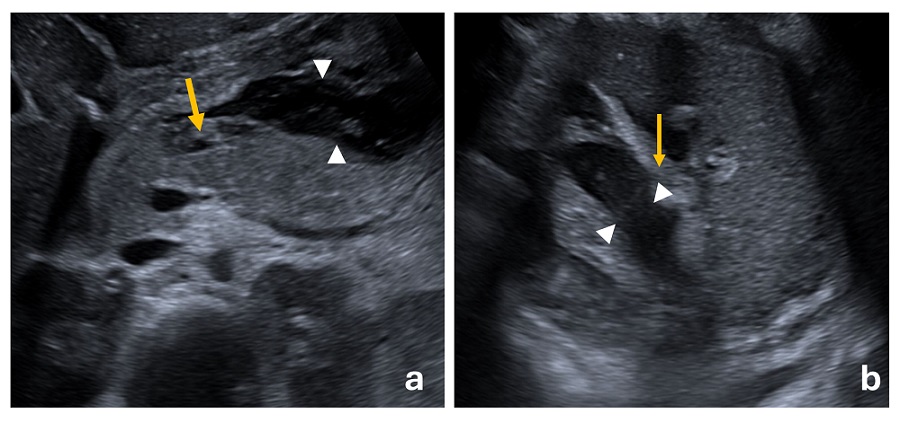

A su llegada a urgencias presenta triángulo de evaluación pediátrica alterado en el lado de la apariencia, con tendencia al sueño. Se encuentra hemodinámicamente estable con constantes en rango y auscultación cardiopulmonar normal. En la exploración destaca abdomen distendido, doloroso a la palpación generalizada, sin signos de irritación peritoneal. Se canaliza acceso vascular periférico y se extrae analítica sanguínea, donde destaca: leucocitosis con neutrofilia (35 000 leucocitos/mm3, 31 400 neutrófilos/mm3), Hb 17,8 g/dl, plaquetas en límite (159 000/mm3) con aumento de reactantes de fase aguda (PCR 145 mg/l), hipoalbuminemia (2,5 g/dl), elevación de LDH 365 U/l, normocalcemia y niveles de ácido valproico en rango terapéutico. Se realiza ecografía abdominal, donde se observa ascitis con dilatación inespecífica de asas intestinales, así como focos de heterogeneidad pancreática (Figura 1a). Se completa el estudio con TAC abdominal, donde, además de lo previo, se evidencia inflamación y heterogeneidad pancreática con focos de necrosis y derrame pleural bilateral. Se amplían enzimas pancreáticas, que están elevadas (amilasa 489 U/l y lipasa 3108 U/l). Es diagnosticado de pancreatitis aguda grave, por lo que es trasladado a UCIP para continuar tratamiento. Se suspende el ácido valproico por sospecha de pancreatitis aguda inducida por fármacos.

| Figura 1. (a) Imagen axial de ecografía abdominal en la cual visualizamos la glándula pancreática aumentada de tamaño con áreas de ecogenicidad heterogénea en cuello-cuerpo pancreático (flecha amarilla) con líquido libre en espacio retroperitoneal, ecogénico y heterogéneo, sin delimitarse una clara pared (Δ). (b) Imagen axial de ecografía abdominal que muestra cambios inflamatorios en la grasa adyacente a la cola pancreática (flecha amarilla) y presencia de líquido libre no coleccionado en dicha localización (Δ). |

Dada la evolución favorable, se inicia nutrición enteral a partir de las 48 horas del ingreso por SNG. Asimismo, inicia ingesta oral de líquidos en pequeñas cantidades. Se repite control ecográfico abdominal a las 72 horas sin desarrollo de complicaciones ni colecciones drenables (Figura 1b). La evolución posterior es favorable, pudiendo suspender meropenem iv tras descartar complicaciones asociadas, y se da alta a los 7 días.